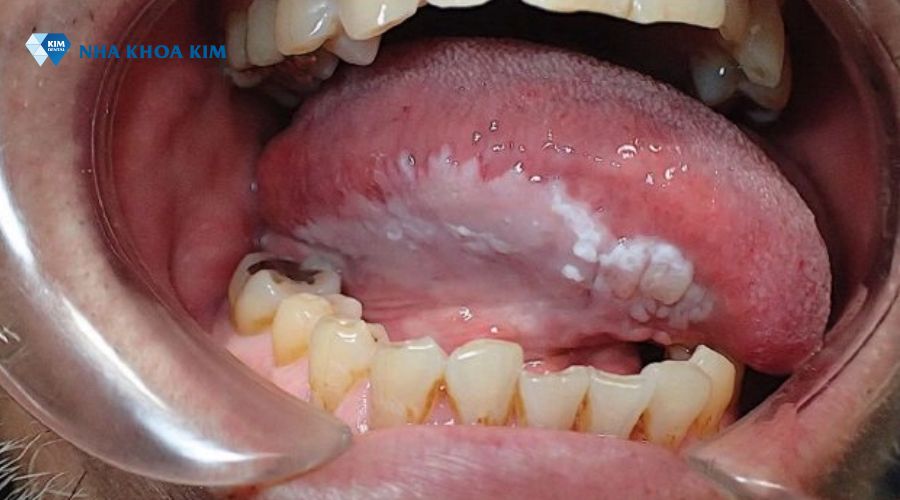

Hình ảnh bệnh bạch sản

Để minh họa rõ hơn, Nha Khoa Kim chia sẻ một số hình ảnh thực tế, giúp bạn nhận diện các mảng trắng bất thường.

Hình ảnh mảng trắng đặc trưng của bệnh Leukoplakia trong khoang miệng

Hình ảnh cận cảnh tổn thương bạch sản lưỡi